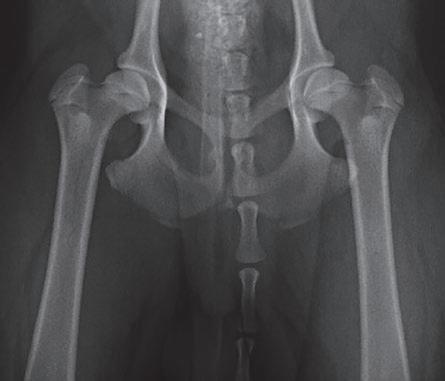

Displasia de cadera (I): etiopatogenia, signos clínicos y pruebas diagnósticas 26